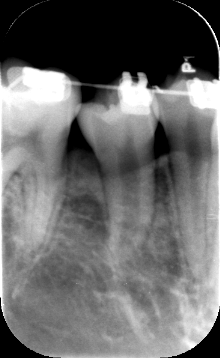

牵引5个月后的牙片

上面很清楚的显示牙根发育完成,位置也被牵引到位了。一年半的时间对于正畸来说,不算最短的,但对于牵引开始,已经算是理想的时间了。因此不论何时开始,只要医患双方互相信任,配合默契,一定能得到理想的结局。